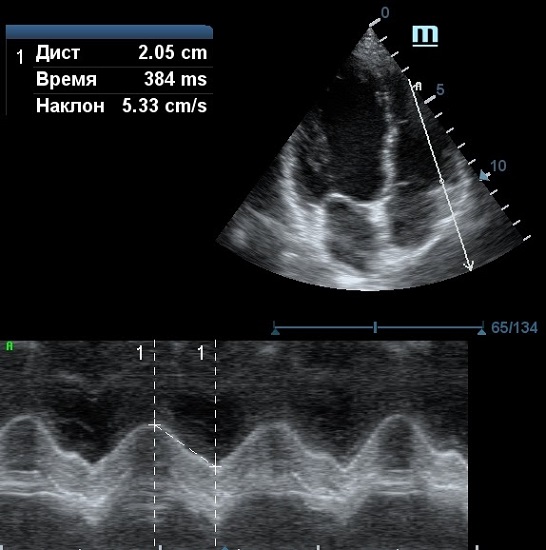

Оценка кооптации нижней полой вены ещё никогда не была такой простой и точной, никаких лишних деталей, просто устанавливаем клипер по анэхогенному участку.